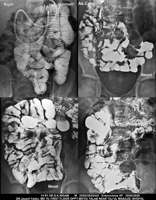

Section: ENTEROCLYSIS

Total: 205 Cases